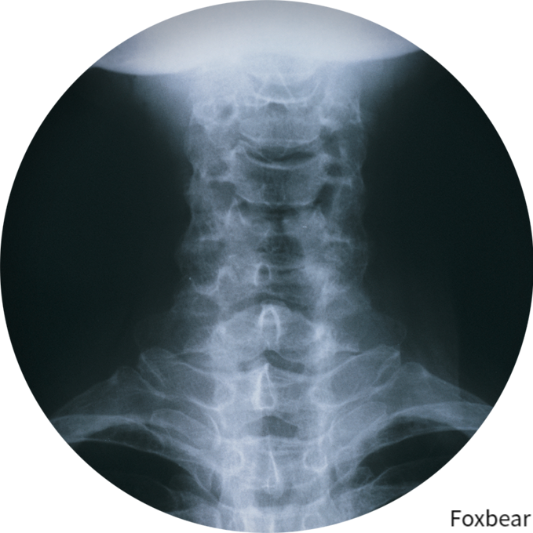

목디스크는 목(경추)의 뼈(척추) 사이에 위치한 쿠션 같은 구조입니다. 건강할 때 이 디스크는 유연성을 제공하고 충격을 흡수합니다. 이러한 디스크에 퇴행, 탈출 또는 기타 문제가 발생하면 이로 인해 다양한 증상이 발생합니다.